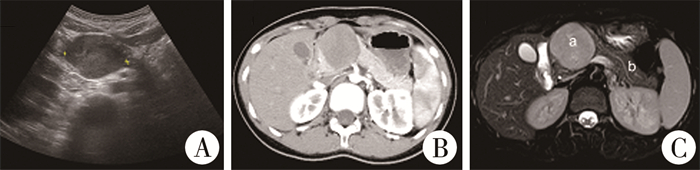

二、影像学检查患儿术前均行超声、全腹增强CT及MRI检查(图 1)。肿瘤位于胰头部2例,体尾部1例,尾部2例;肿瘤长径2.6~5.6 cm(中位长径为4.00 cm),均未发现周围组织侵犯及远处转移。

图 1 胰腺实性假乳头状瘤影像学检查图片 Fig.1 Images of pancreastic solid pseudopapilloma 注 A:胰头部低回声包块,边界清楚,形态欠规整,内部回声不均匀;B:胰头部类圆形占位,边界尚清,密度欠均匀, 增强见强化;C:胰头部稍长T1稍长T2信号肿块影(a),边界清晰,与胰管位置密切,胰管稍扩张(b) |